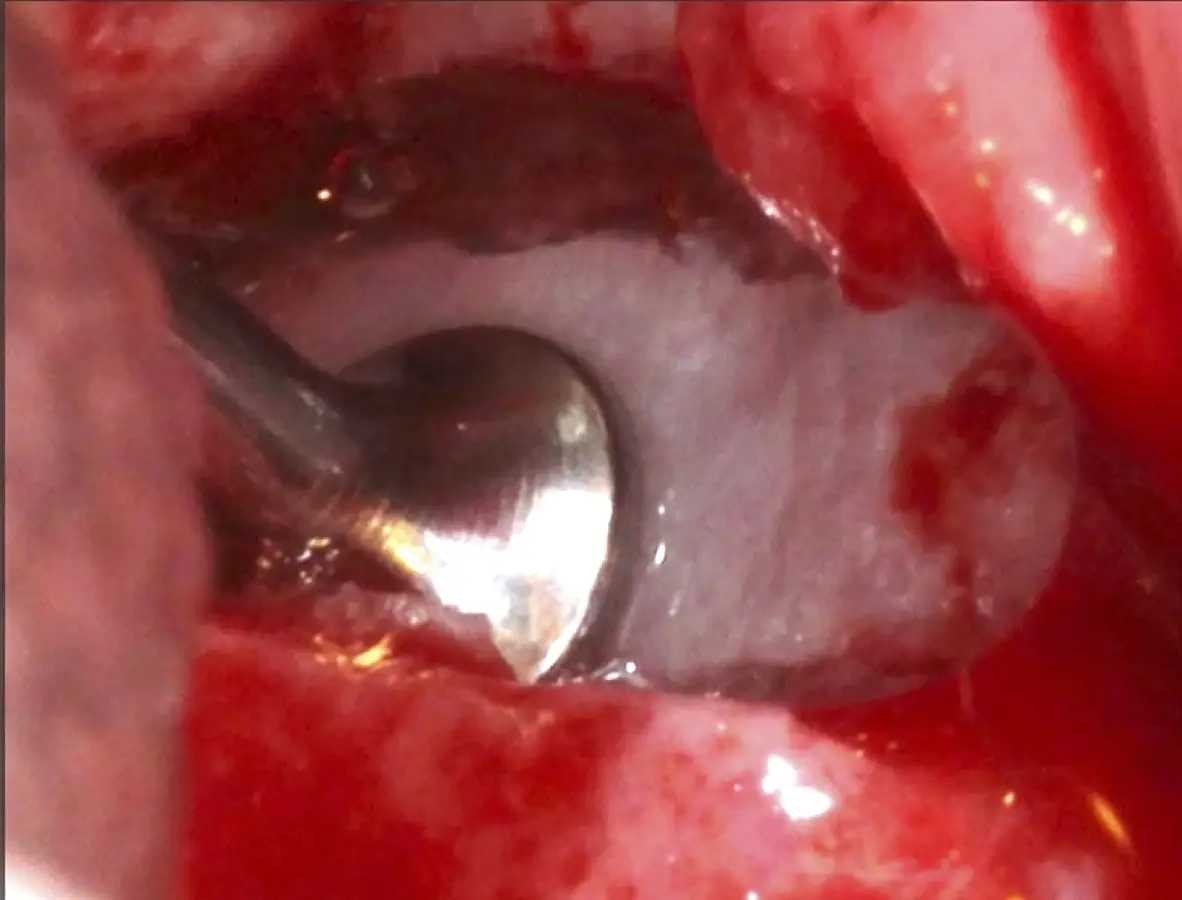

Se inicia la elevación de la membrana de Schneider con el inserto redondeado no cortante en forma de disco, empleando movimientos suaves. El levantamiento puede complementarse con elevadores convencionales, siguiendo la dirección mesiodistal. La fase de desprendimiento inicia con el piso y sigue hacia la pared mesial para terminar, y de ser necesario, hacia la pared posterior. Existen diversos insertos con angulaciones y longitudes para mayor accesibilidad16 (Figura 1).

Figura 1. Incisión y levantamiento de colgajo a espesor total.